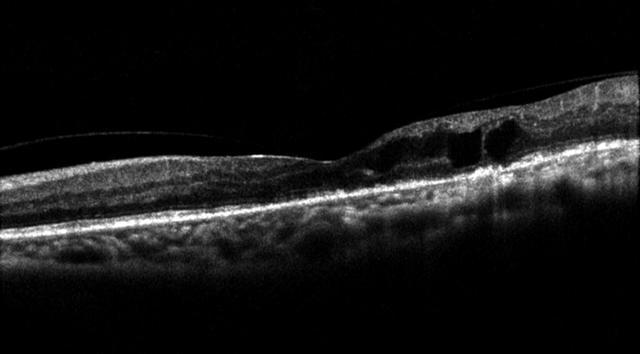

黄斑水肿oct图片,黄斑变性OCT读图

糖尿病性黄斑水肿的oct表现1)糖尿病性黄斑水肿4.

oct:右眼黄斑水肿较前稍好转iva第二针术后1个月复诊

患者黄斑oct图

眼底黄斑水肿的oct表现

黄斑水肿oct图片解释

黄斑水肿oct的详细图解